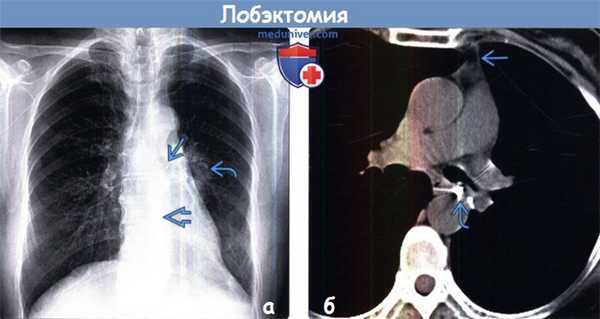

Лобэктомия и субдолевая резекция (объединяет клиновидную резекцию и сегментэктомию) являются менее масштабными процедурами, которые могут быть идентифицированы по объемному уменьшению легкого и наличию хирургических скоб.

(б) Пациент, перенесший верхнедолевую лобэктомию слева. На совмещенных изображениях при КТ с контрастным усилением в легочном (слева) и мягкотканном (справа) режимах визуализируются культя левого верхнедолевого бронха >i и хирургические скобы. Следует отметить смещение влево переднего средостения вследствие объемного уменьшения левой половины грудной полости.

о Левосторонняя верхнедолевая лобэктомия:

- Объемное уменьшение левого легкого

- Новообразованная междолевая щель отсутствует

- Высокое расположение корня левого легкого

- Угол бифуркации трахеи уменьшен

- Переднее средостение смещено влево

- Выявляется юкстадиафрагмальный пик в левом куполе диафрагмы

- Гипервентиляция нижней доли левого легкого (НДЛЛ)

(а) Пациент, перенесший левостороннюю верхнедолевую лобэктомию. При рентгенографии органов грудной клетки в /7/7 проекции определяются объемное уменьшение левого легкого, высокое расположение корня левого легкого и смещение влево верхних отделов средостения.

(б) У этого же пациента на совмещенных изображениях при КТ с контрастным усилением визуализируются смещение влево переднего средостения и хирургические скобы в культе верхнедолевого бронха.. При левосторонней лобэктомии междолевая щель не формируется.